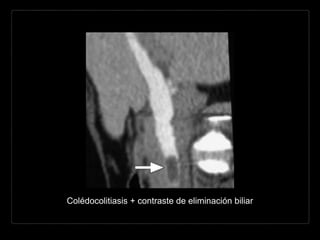

Hallazgos por TC

• densidad del cálculo

aire - < agua - tejidos blandos -

calcio

• mixtas: anillo calcificado y nido central

• ↑ atenuación (75-85%)

• signo “ojo de buey”: anillo de bilis rodeando un cálculo en un

conducto

• colesterol puro = isodensas con la bilis

• terminación abrupta del colédoco

• dilatación de la VBIH y EH

• Cálculos

• posición posterior (dependiente)

• semiluna de bilis o aire rodeando la

porción anterior del cálculo

• forma geométrica o angulada

• apariencia multilaminar

• signos de inflamación

• edema periductal, engrosamiento

epitelial biliar y reforzamiento

mural.

• mejor valoración

• cortes delgados y MPR

• contraste oral (-) > (+)

• oscurecimiento litos

ampulares

• parámetros altos del

tubo 140 kVp

• litos hiperdensos >

bilis

Colédocolitiasis + contraste de eliminación biliar

2 mm